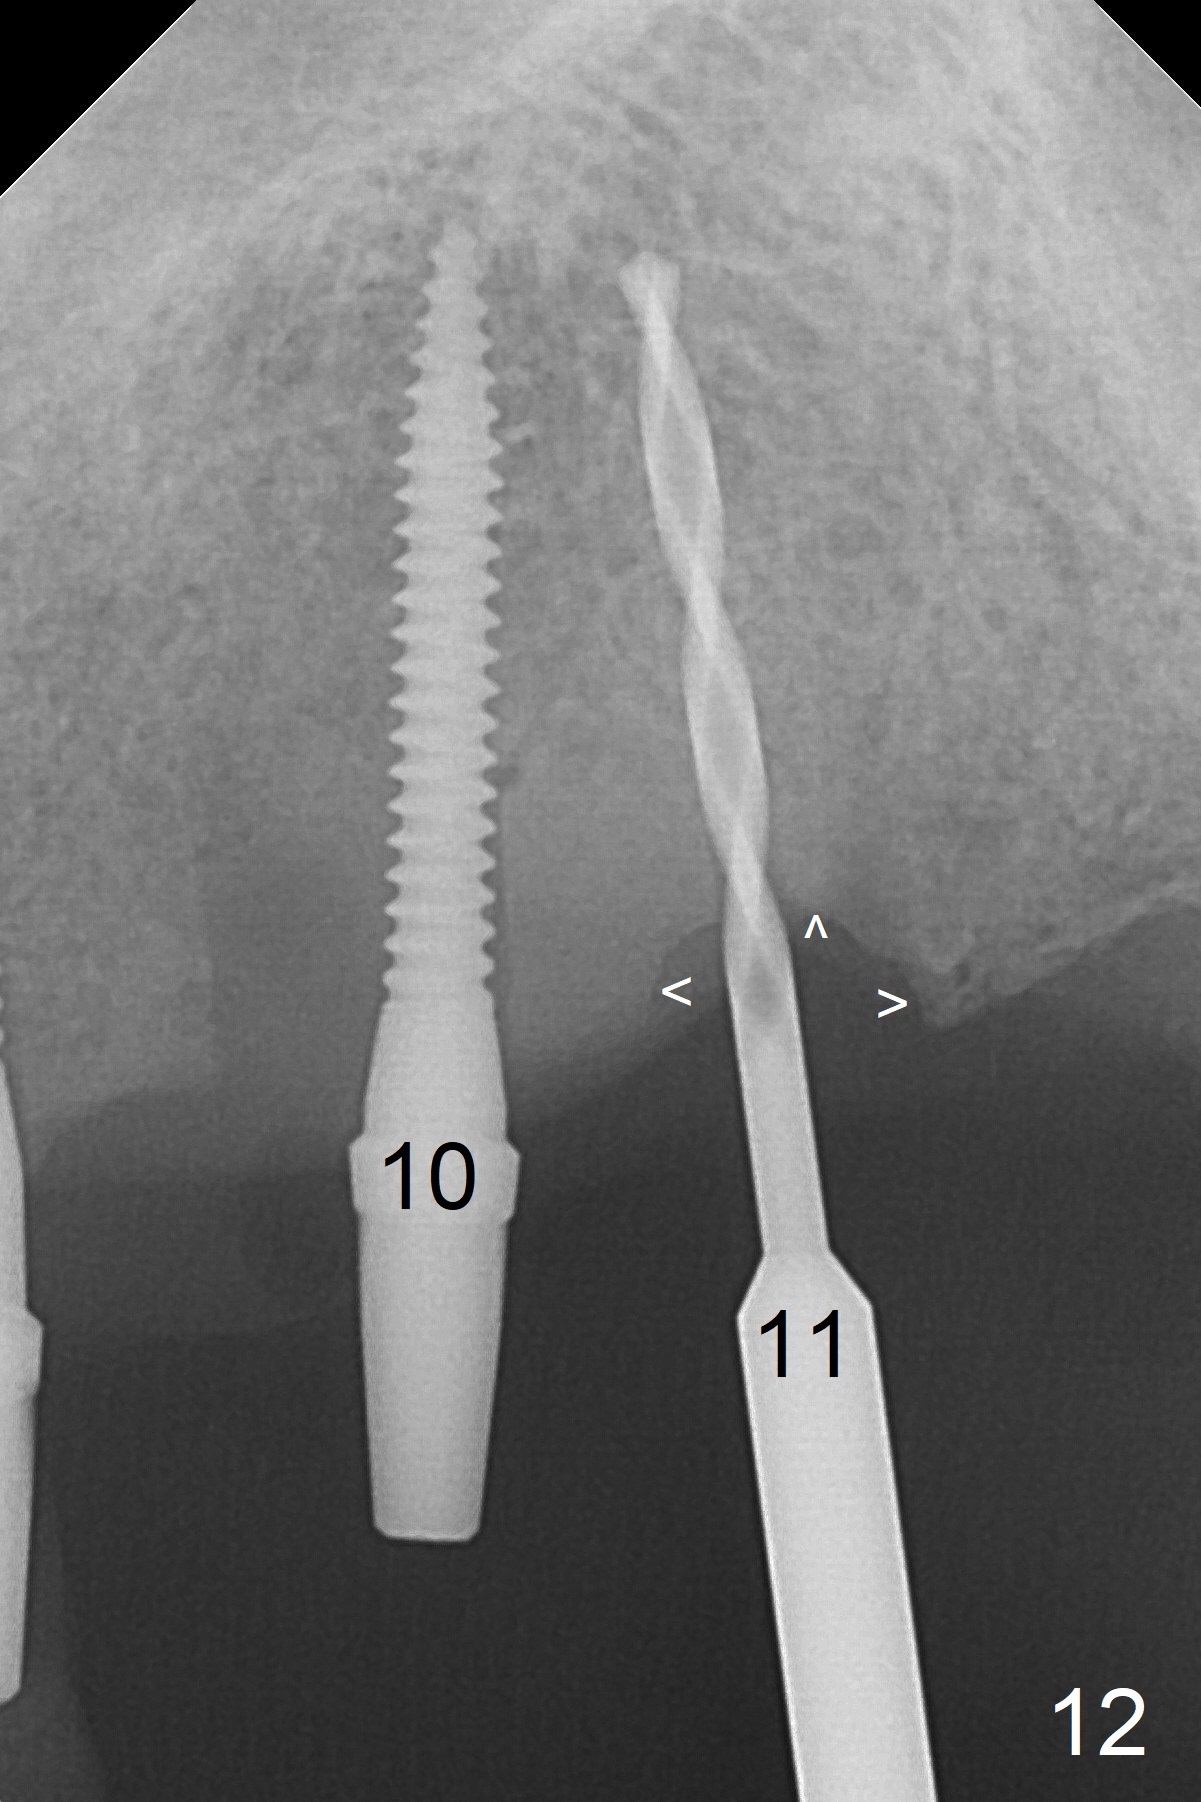

At the sites of #11 and 12, the knife-edged ridge is trimmed prior to initiation of osteotomy (Fig.12,13). With the flattened ridge, it is easy to start osteotomy and control the mesiodistal position. When the position and the trajectory are not correct, they can be changed (Fig.14-16) with 2.5x14(4), 2.5x12(2) and 3x10(2) mm implants placed at #11,12, and 13, respectively. With relatively correct position of each implant, it would be easy to fabricate a splinted 6-unit provisional.